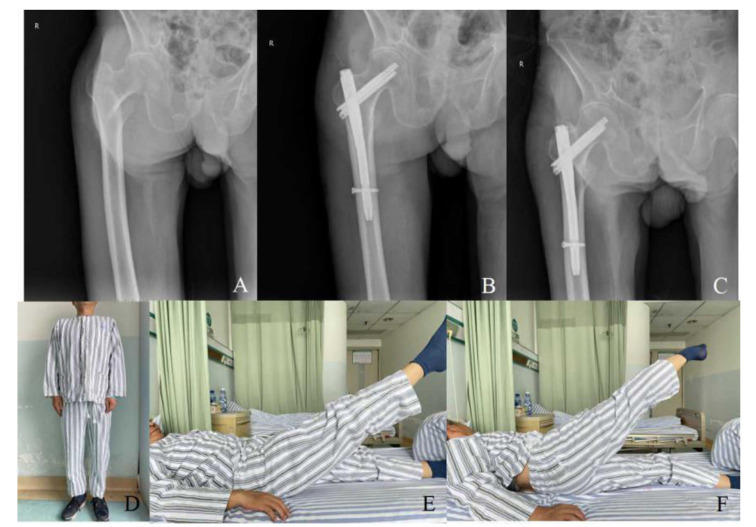

Methods: Eighty-two elderly patients with intertrochanteric femoral fractures treated at Xiangyang No. 1 People's Hospital affiliated with Hubei University of Medicine from December 2021 to 2022 were retrospectively analyzed. They were categorized into three surgical groups: PFBN (22 cases), Inter-TAN (20 cases), and PFNA (40 cases). Preoperative demographics and fracture characteristics were compared, alongside intraoperative and postoperative metrics like operative time and complication rates.

Results: In the PFBN group, operative time, fluoroscopy use, blood loss, and transfusion were higher, but postoperative weight-bearing, healing, and hospital stay were shorter compared to the Inter-TAN and PFNA groups (P<0.05). Inter-TAN had a significantly shorter postoperative weight-bearing time than PFNA (P<0.001). Other compared factors showed no significant differences between groups (P>0.05), including complication rates and scores at 6-month follow-up.

Conclusions: PFBN, a novel surgical approach for intertrochanteric fractures in elderly patients, outperforms Inter-TAN and PFNA by accelerating early weight-bearing and hastening fracture recovery.